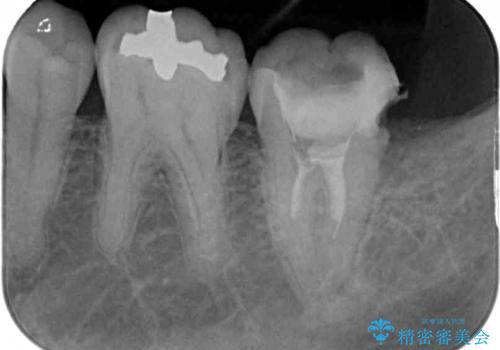

既に根管治療を終えている状態での来院で、クラウンを装着を希望されていらっしゃいました。

レントゲン写真より根管治療のやり直しをお勧めしたところ、ラバーダム使用下で処置を行うことを希望されたため、根管治療を行った後にオールセラミッククラウンにて補綴治療を行うこととしました。